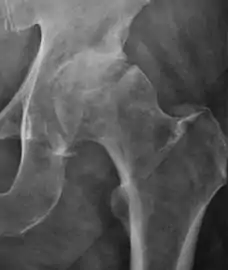

Projectional radiography ("X-ray") is the first imaging technique of choice in hip pain, not only in older people with suspected osteoarthritis but also in young people without any such suspicion. In this case plain radiography allows categorization as normal hip or dysplastic hip, or with impingement signs, pincer, cam, or a combination of both.[1]

Projectional radiography ("X-ray") is currently useful not only in older people in whom osteoarthritis of the hip is suspected but also in younger people without osteoarthritis, who are being evaluated for femoroacetabular impingement (FAI) or hip dysplasia.[1]

Plain radiography allows us to categorize the hip as normal or dysplastic or with impingement signs (pincer, cam, or a combination of both). Besides these, pathologic processes like osteoarthritis, inflammatory diseases, infection, or tumors can also be identified (Figure 1).[1]